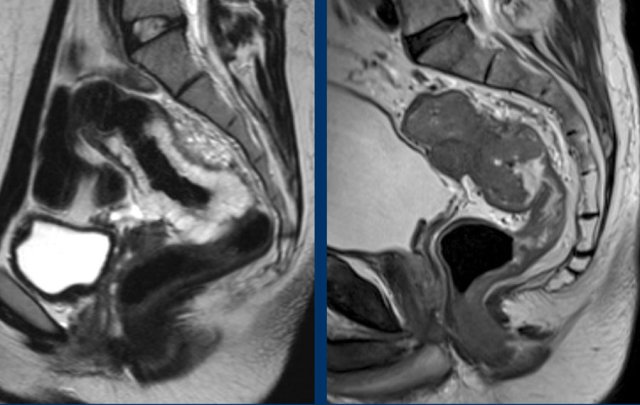

In 2019 an international consensus panel agreed on the “sigmoid take-off” as the preferred landmark to define the rectosigmoid junction and separate the rectum from the sigmoid on imaging (ref).

The sigmoid take off can be recognized on sagittal MRI as the point from which the sigmoid sweeps horizontally away from the sacrum.

The sigmoid take-off can be recognized on sagittal MRI as the point from which the sigmoid sweeps horizontally away from the sacrum and on an axial view as the point from which the sigmoid projects ventrally (figure).

Though recognizing the sigmoid take-off on imaging may be challenging in some cases due to anatomical variations between patients or varying sequence angulation, it is overall an intuitive landmark.

Tumors above the level of the rectosigmoid junction with a lower border starting proximal to the sigmoid take-off are considered sigmoid tumors.